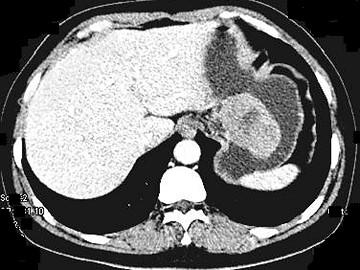

- 单项选择题女,51岁, 上腹部隐痛不适,CT检查如图, 最可能的诊断是 ( )

A、胃癌

B、胃息肉

C、胃腺瘤

D、胃溃疡

E、胃间质瘤